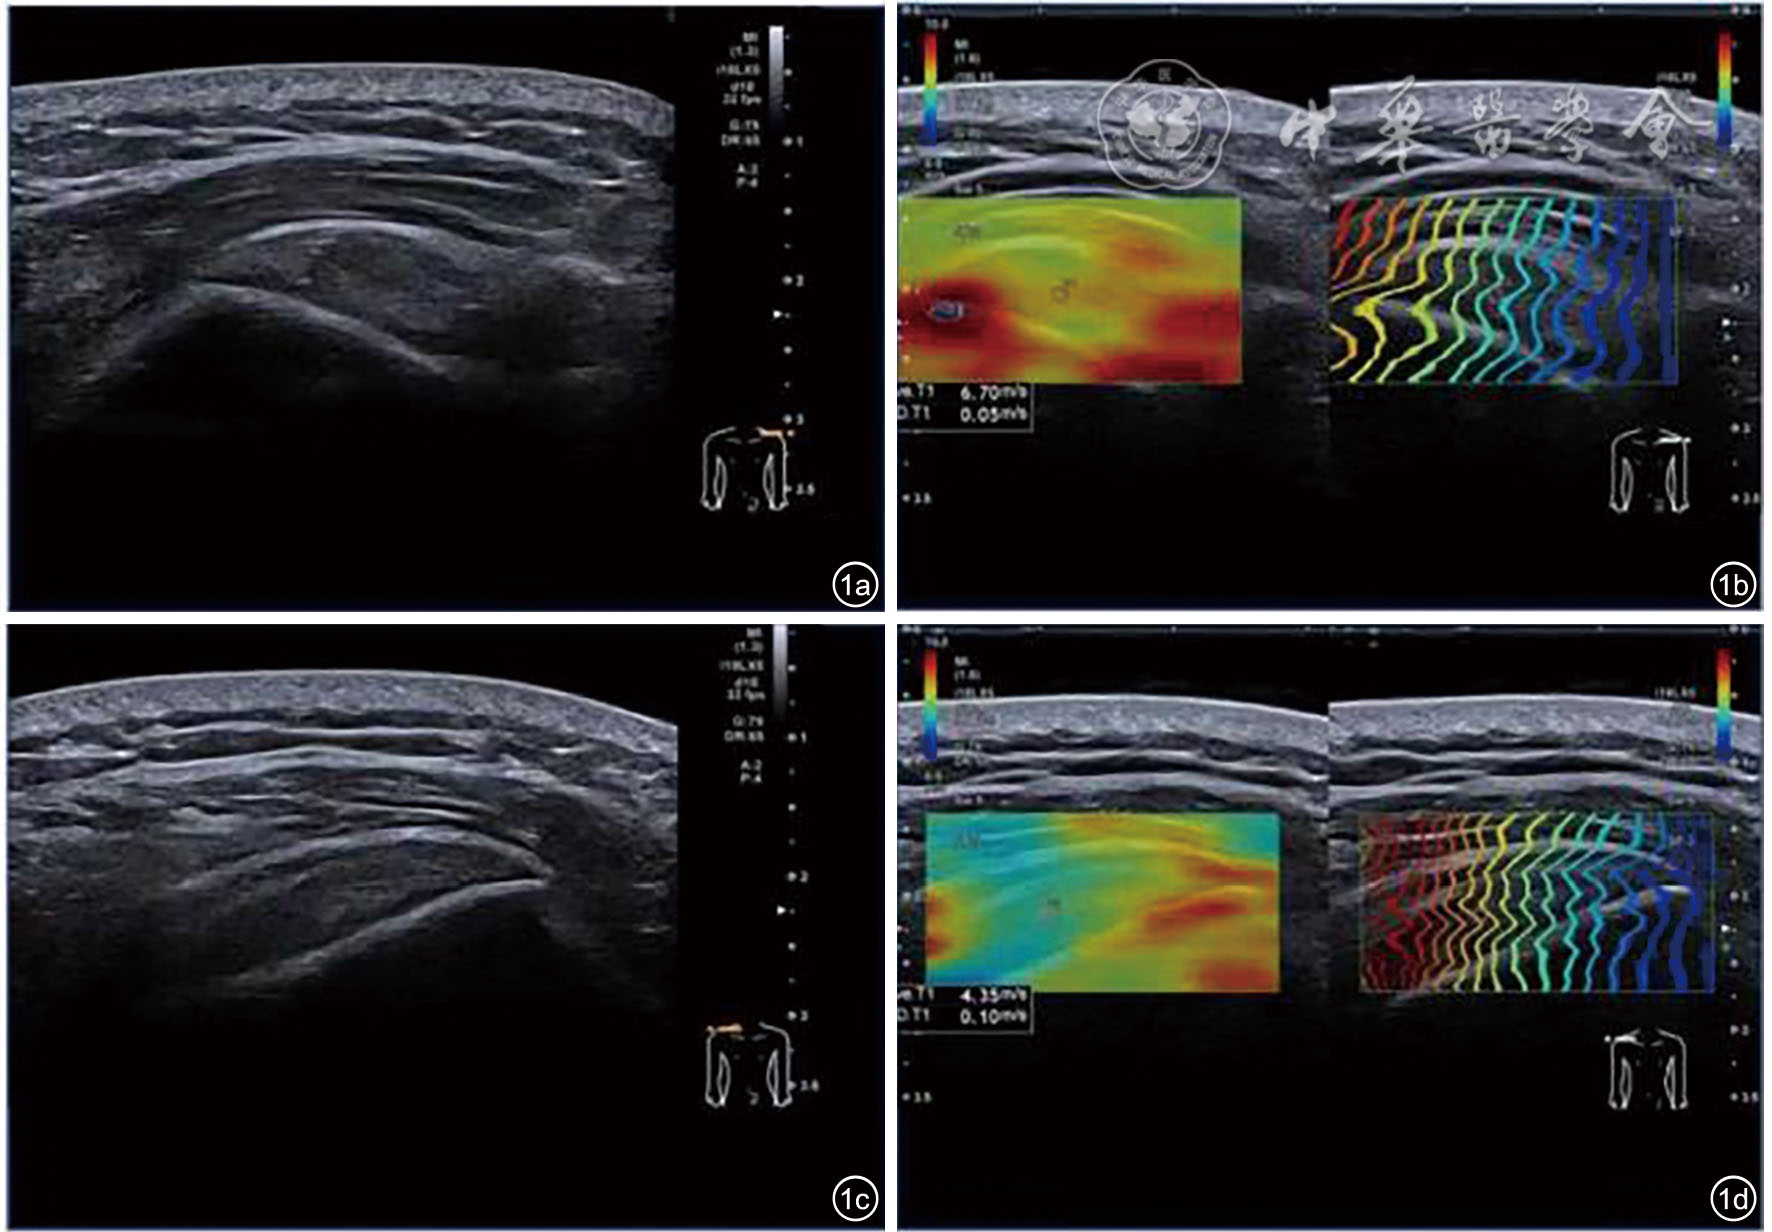

图1 右侧慢性冈上肌腱病患者双侧冈上肌腱的灰阶超声与剪切波弹性成像对比图。图a为左侧(健侧)冈上肌腱灰阶超声图;图b为左侧(健侧)冈上肌腱剪切波弹性成像图;图c为右侧(患侧)冈上肌腱灰阶超声图;图d为右侧(患侧)冈上肌腱剪切波弹性成像图。两侧冈上肌腱连续性尚可,未见明显异常;但在剪切波弹性成像图中,病变肌腱区域颜色分布不均,肌腱中心区剪切波速度降至4.35 m/s(健侧6.70 m/s),提示组织弹性显著下降,反映出剪切波速度可早期识别肌腱力学变化